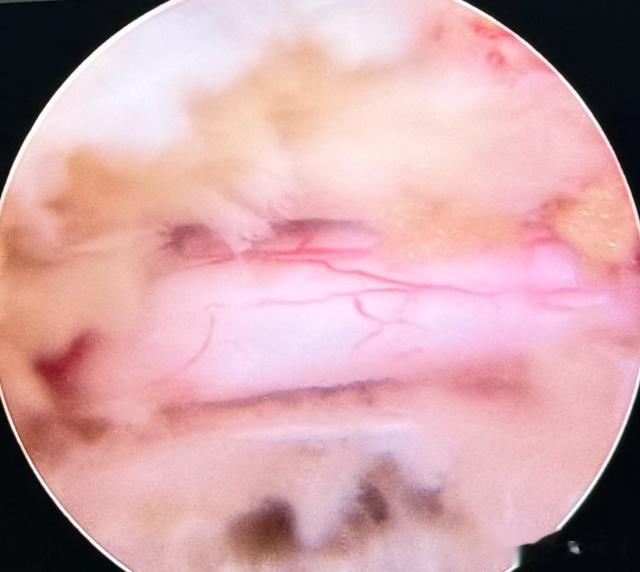

面部巨大的缺损,则采用皮瓣移植——从老人颈部借一块完好的皮肤和皮下组织,旋转覆盖到面部创口上,这将是墨江县医院历史上第一例如此复杂的皮瓣修复手术。

当最后一层纱布被轻轻揭开,老人颤抖着抬起手,摸向自己的脸颊,触手可及的,不再是那个令人作呕的巨大凸起,而是一片平整,干净的皮肤。

他张了张嘴,似乎想说什么,最终只是紧紧、紧紧地拉住徐赫的手,老泪纵横,谢谢,谢谢你们,这下,我能干干净净地活着,也能干干净净地走了。